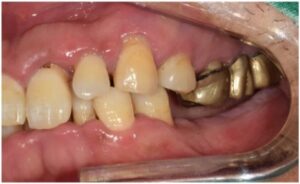

먼저 구강 내를

확인해 보았더니

만성 치주염으로 인해

잇몸이 부어있고

기구로 건드리기만 해도 피가 날 정도

잇몸 상태가 많이 좋지 않으셨는데요.

오늘 소개해 드릴

환자분께서는

50대 남성분으로

아래턱 양측 어금니는 상실되었고,

위턱 양측 어금니는 흔들리고 불편하시다며

전체적인 치료를 위해

내원해 주셨는데요.